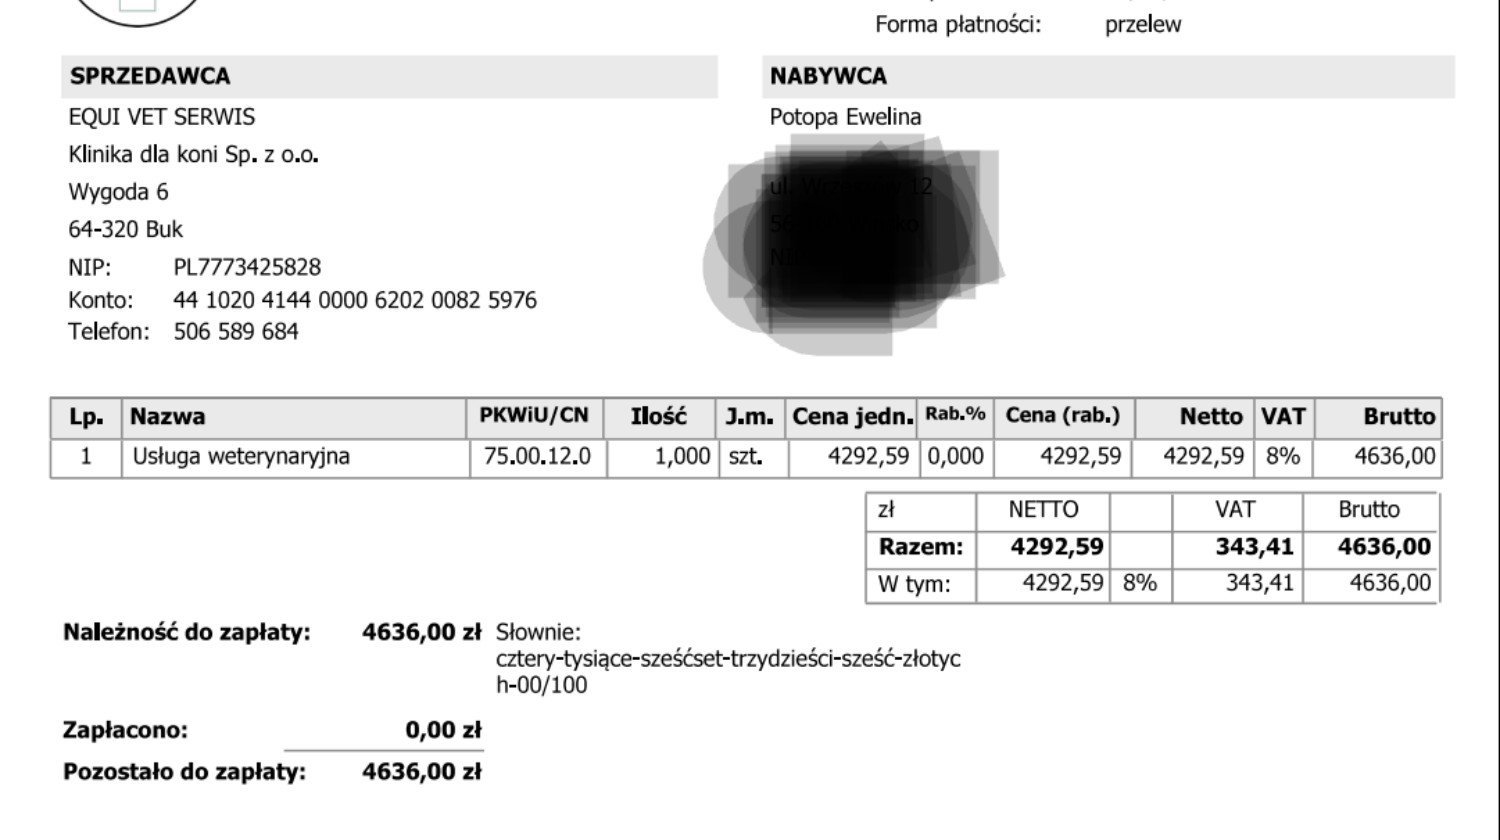

Aktualizacja 30.05

Załączam screeny faktur z kliniki. Koń przeszedł operację bez komplikacji, za około trzy miesiące będzie wiadomo coś więcej.